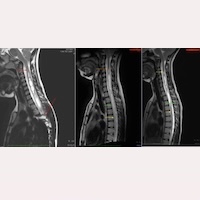

Avant l’intervention, ses IRM du 25/03/2015 démontraient : Maladie du filum et Syndrome Neuro-crânio-vertébral avec descente des amygdales cérébelleuses (Syndrome d’Arnold-Chiari I), syringomyélie et scoliose idiopathiques. La télémétrie du rachis montrait : scoliose dextroconvexe au niveau dorsal et lévoconvexe au niveau lombaire, ainsi qu’une rectification de la lordose cervicale.

Dans son dossier médical, dès le contrôle de la première année postopératoire, une diminution de la cavité intramédullaire avait été notée, qui s’est encore améliorée au cours des années suivantes, jusqu’à aujourd’hui, lorsque C. vient à l’ICSEB pour son contrôle à 10 ans.

Lors de son suivi comparatif par IRM, on peut observer :

Actuellement, à 17 ans et lors du contrôle postopératoire à 10 ans, C. rapporte ne plus présenter la majorité des symptômes préopératoires (90 %), et le spécialiste souligne la récupération de la majorité des signes neurologiques, ainsi que la nette diminution de la cavité intramédullaire et la disparition de la courbure scoliotique.